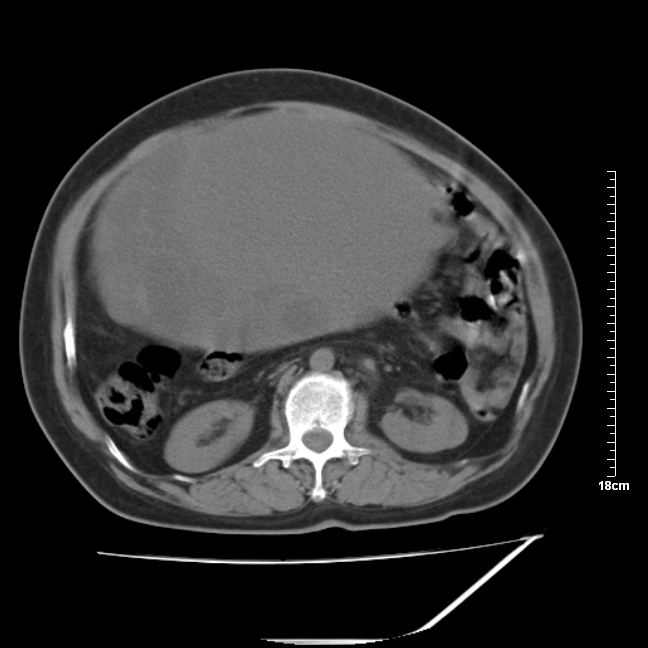

以下是引用jinning在2007-5-17 11:18:00的发言:[br]考虑右侧卵巢囊腺瘤合并少量出血可能性大